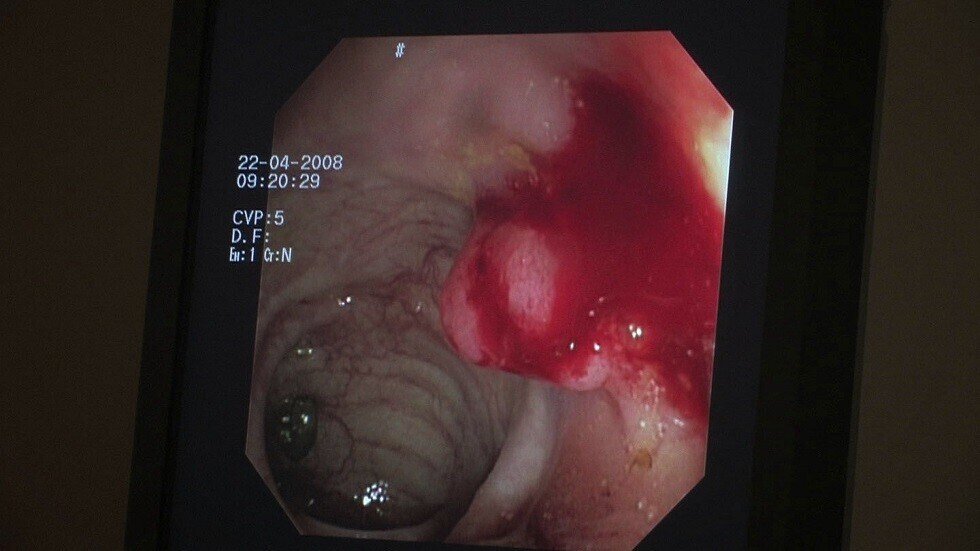

كيف نخفض من خطر "بوليب" الأمعاء؟

بعض "البوليب" الذي ينمو في الأمعاء ينذر بتحولها إلى أورام سرطانية. وقد بينت نتائج دراسة حديثة كيف يمكن تخفيض خطر تحولها إلى ورم سرطاني بواسطة جهود شخصية.

نشر الباحثون نتائج دراستهم في مجلة British Journal of Cancer، يؤكد مؤلفوها على أن خطر ظهور "البوليبات" ينذر بالإصابة بسرطان الأمعاء، ولكن يمكن تخفيض هذا الخطر بممارسة نشاط بدني منتظم.

درس الخبراء بيانات تم الحصول عليها خلال إجراء الدراسة الثانية لصحة الممرضات التي شملت 28250 امرأة من مختلف الأعمار. خضعت جميع المشتركات في الدراسة إلى كشف المعي المستقيم أو القولون بالكامل باستخدام المنظار. نتائج هذا الكشف قارنها الباحثون بالأمراض التي شخصت لدى المشتركات وكذلك مع العادات السيئة (التدخين، تعاطي الكحول، التغذية السيئة)، والنشاط البدني والحمل وغيرها من العوامل الحياتية.

كشف الأعراض الرئيسية لسرطان الأمعاء

اتضح من نتيجة هذه الدراسة، أن خطر نمو "البوليبات" في الأمعاء يرتبط بصورة ما بالنشاط البدني. فقد تبين أن النساء اللواتي كن يمارسن نشاطا بدنيا ويتحركن كثيرا أو يمارسن نوعا من أنواع الرياضة في مرحلة الطفولة أو بعدها من عمر 12 سنة إلى أن بلغن 64 سنة وأكثر من العمر انخفض خطر نمو "البوليبات" عندهن بنسبة 24%.

دراسة: الزبادي تحمي الرجال من خطر سرطان الأمعاء!

أما اللواتي يمارسن في اليوم نشاطا بدنيا لمدة ساعة في حياتهن من عمر 12 سنة إلى أن بلغن 22 سنة فقد انخفض خطر "البوليبات" بنسبة 7%. والنساء اللواتي كن يمارسن النشاط البدني من عمر 13 سنة إلى عمر 64 سنة فقد انخفض هذا الخطر بنسبة 9%.

المصدر:ميديك فوروم